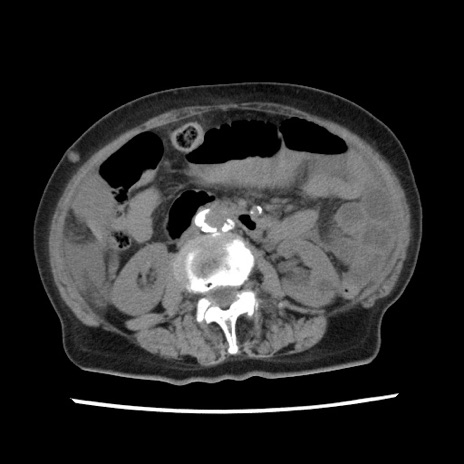

矢状断像

【症例】80歳代女性

【主訴】腹痛

【現病歴】8時間前から腹痛あり来院。

【既往歴】糖尿病、脂質異常症、子宮体癌にて子宮全摘術

【身体所見】意識清明・会話良好だが腹痛で苦悶様、全腹部にわたって反跳痛と圧痛あり

【データ】WBC 13600、CRP 0.14、LDH 224、CK 90